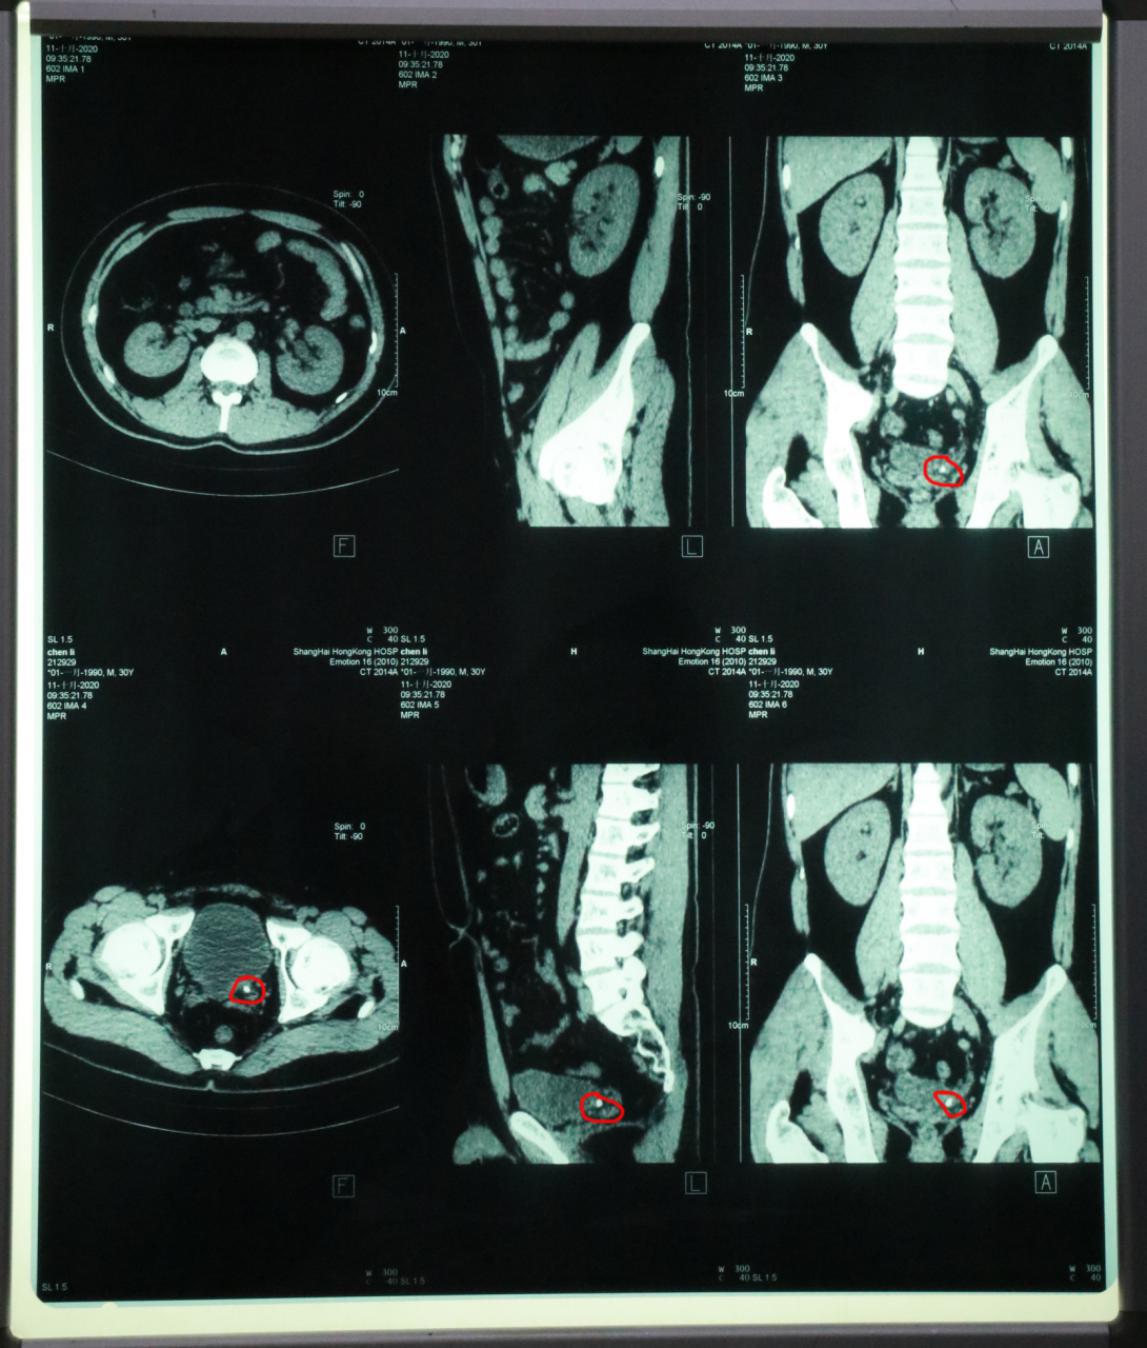

陈主任听完小王的陈述,判断可能为输尿管结石,马上给予泌尿CT及血尿常规检查,半小时后CT报告显示,右输尿管下段有一粒约0.7cm的结石并伴右输尿管扩张及右肾积水。陈主任根据病人的诊断结果,建议病人做体外超声波碎石及解痉止痛对症治疗。

陈主任介绍:小王的结石是典型的输尿管结石,是在上下楼梯这种工作运动中,导致结石由肾内掉入输尿管引发剧烈的疼痛并伴有恶心呕吐。这种疼痛很剧烈,相当于八根肋骨同时断裂的程度;有肾绞痛的时候不要熬不要忍,因为结石可以擦伤输尿管粘膜,出现血尿,而血尿容易造成尿路感染,时间久了易形成脓肾;疼痛时间越长,感染机会越多,所以一旦发现肾绞痛,就需要立即来医院就医,让医生诊断后制定治疗方案,加速结石的排出,减少对肾脏的危害。

经过陈主任的治疗,小王的疼痛慢慢缓解,逐渐消失,最后一次复查CT检查结果显示泌尿系统内已经没有结石的存在,让小王备受折磨的结石已被排出体外。经过这次经历,小王也明白了有疾病后千万不要忍不要熬,一定要积极治疗。